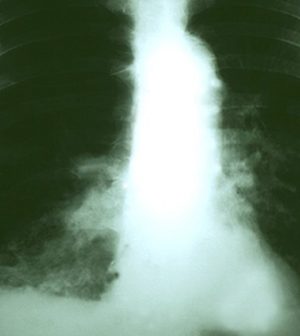

A low-dose CT scan is the standard diagnostic test for people at high risk of lung cancer. In the United States, about one-quarter of these scans reveal shadows indicating nodules in the lung. Despite that positive result, fewer than 4 percent of those patients actually have cancer.